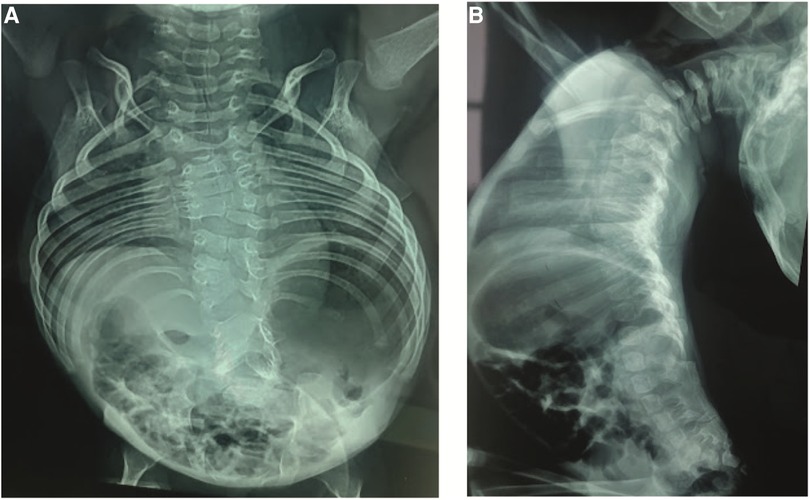

Anteroposterior (AP) and lateral x-rays of the entire spine showed multiple vertebral segmentation defects with irregularly shaped vertebrae, bloc vertebrae, rachischisis, and multiple hemivertebrae defects affecting the whole spine with fusion of the spinal processes and a hyperlordosis that spans the entire spine. The ribs fan out from the vertebra in a “crab-like” fashion. There was no frontal deformity of the spine (Figure 2).

FIGURE 2

Figure 2. (A) Anteroposterior x-rays view showing the multiple vertebral defects and the “crab-like” aspect of the rib cage. (B) Lateral view showing the hyperlordosis and the fusion of the spinal processes.